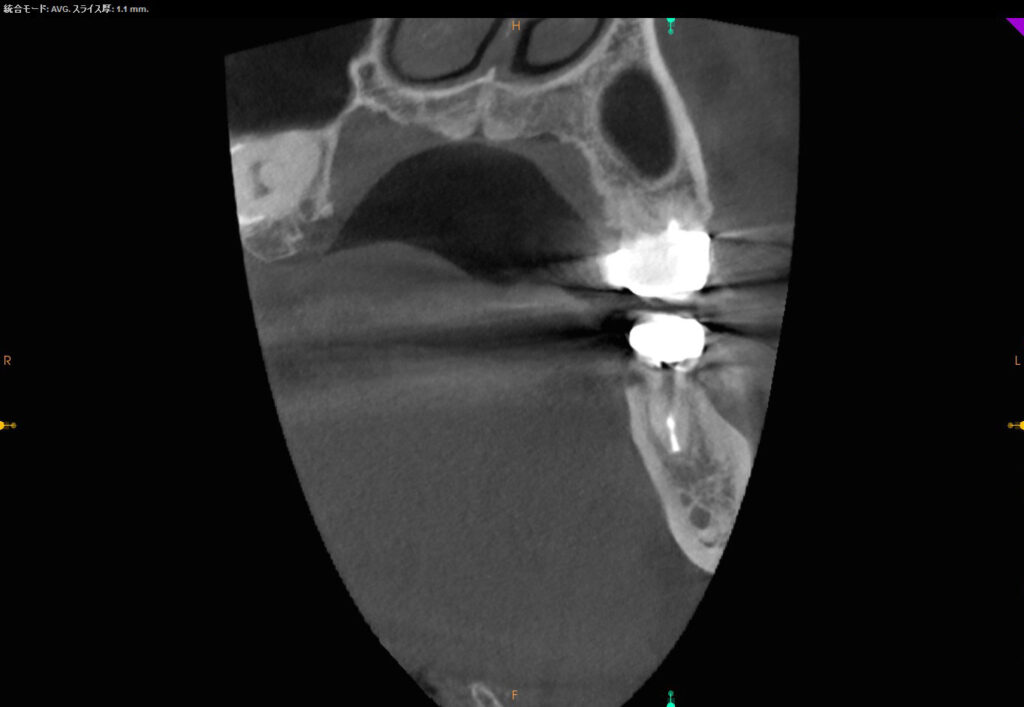

CT画像前頭断

舌側の骨吸収像が改善され、固い皮質骨(顎骨の表層の骨)が形成していることがはっきりと分かります。また、根っこの先の透過像も改善されています。